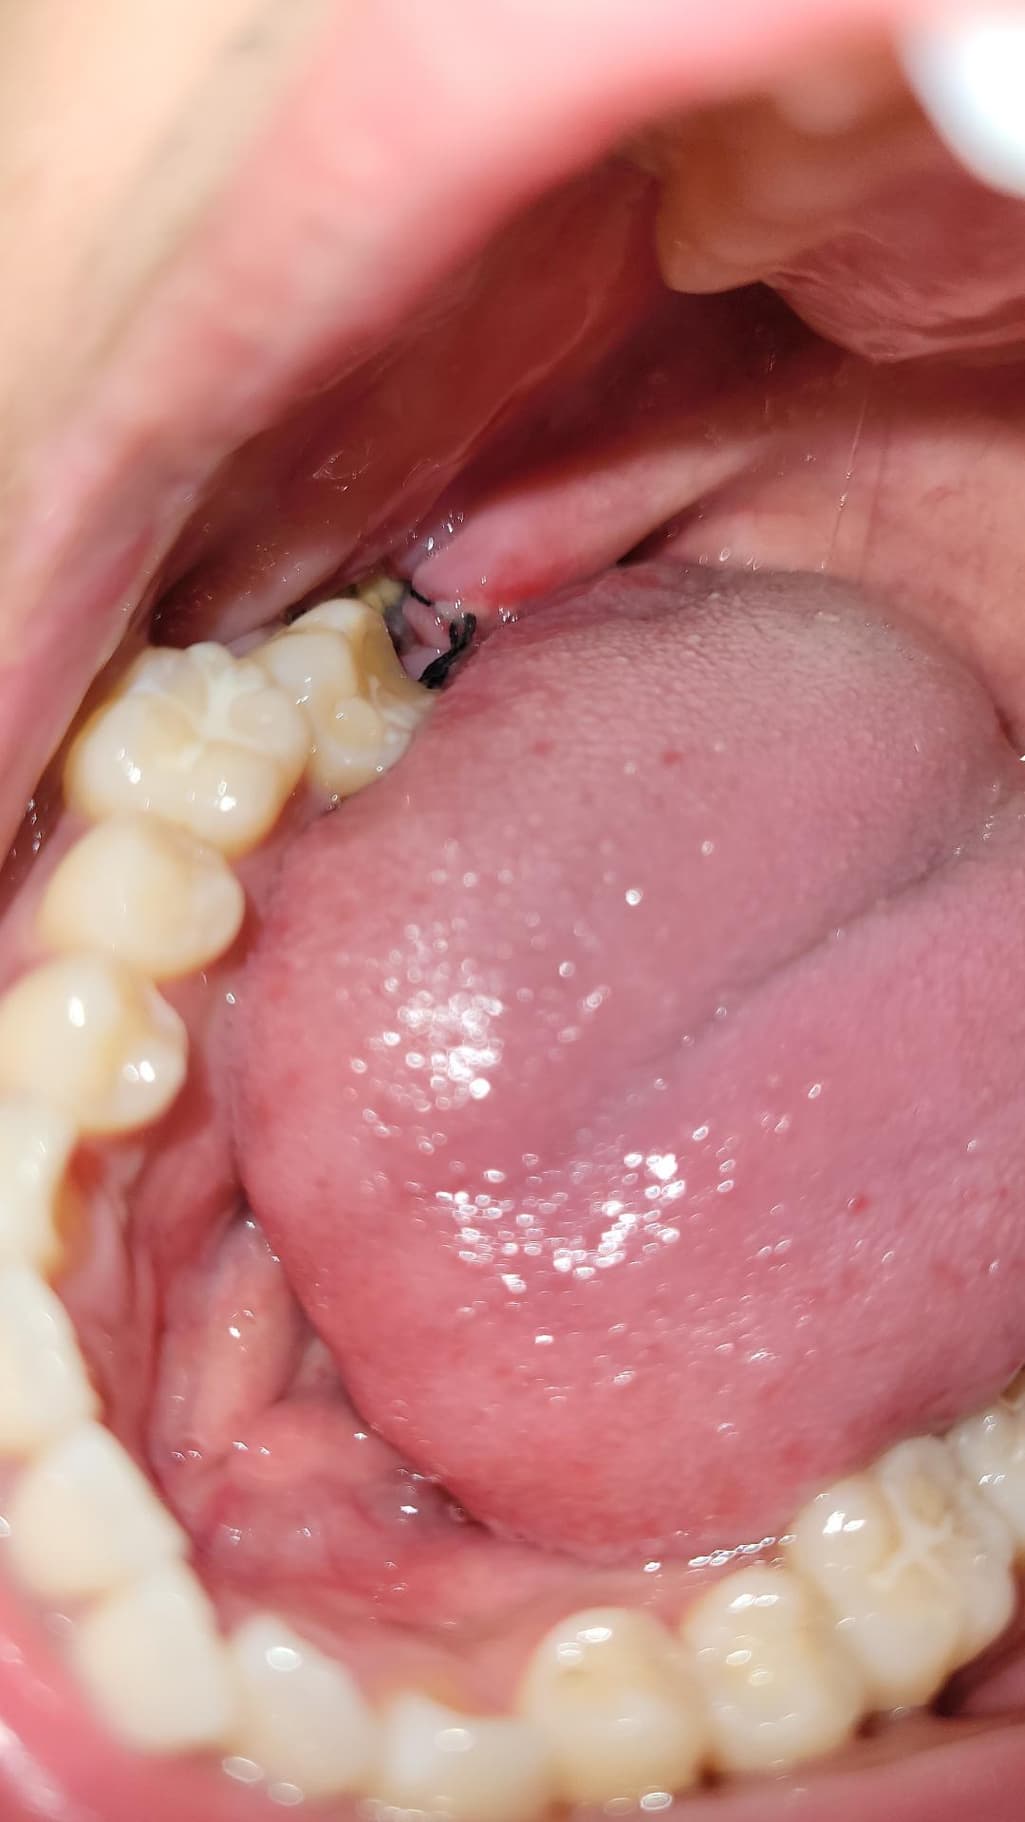

이거 혹시 드라이소켓 같은건가요?? 실밥이 풀린건가요...

이게 실밥이 풀린건지 안에 흰색이 보여서 그러는데 이게 멀까요... 아 진짜 사랑니 뽑은지는 3일 됐는데 바로 치과 가야할까요?? 아니면 어떡해야할까요

하얀색은 잇몸이 치유되는 조직으로 보이고, 실밥은 느슨해진 상태입니다. 드라이소겟은 참을수 없는 통증이 동반됩니다. 염려가 된다면 치과에 내원하여 소독을 받는것도 좋을것 같습니다. 건강하세요.

흰색 보이는 건 치유과정에서 생기는 염증,육아조직 같습니다

실밥은 밥먹다가, 양치하다가 지연스럽게 풀리기도 합니다